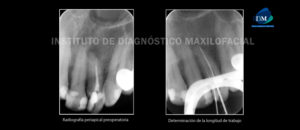

Es bien sabido que el éxito de la terapia endodóntica depende de la limpieza y conformación completa de los sistemas del conducto radicular, la obturación